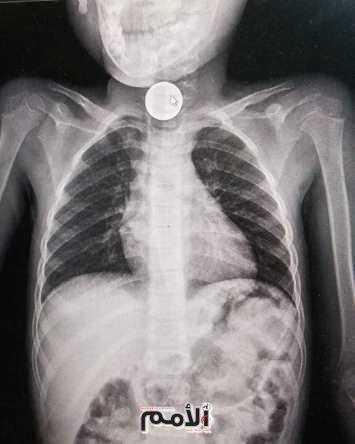

وأوضح رئيس دائرة الأطفال بمستشفى الملكة رانيا العبدالله العميد الطبيب عبدالله غنما، أن إبتلاع الأجسام الغريبة مشكلة شائعة لدى الأطفال خصوصاً من عمر عام لعشرة اعوام، وأضاف أن تم إزالة انواع مختلفة من الأجسام الغريبة من جسم الأطفال مثل العملات المعدنية والكرات الزجاجية وبعض الأجسام الحادة وبطاريات الالعاب.

وبين العقيد الروله بأن الأجسام الغربية تمثل خطراً على حياة الطفل لما تسببه من مضاعفات خطيرة، فقد تؤدي لتضيق بالمرئ أوعمل ثقب بالمرئ من خلال بطاريات الألعاب المبتلعه، أضافه لانسداد بالأمعاء من خلال العملات المعدنية، وأضاف الروله ان العمليات اجريت بمشاركة المقدم الطبيب محمد الشطناوي، والرائد الطبيب محمد القرعان.